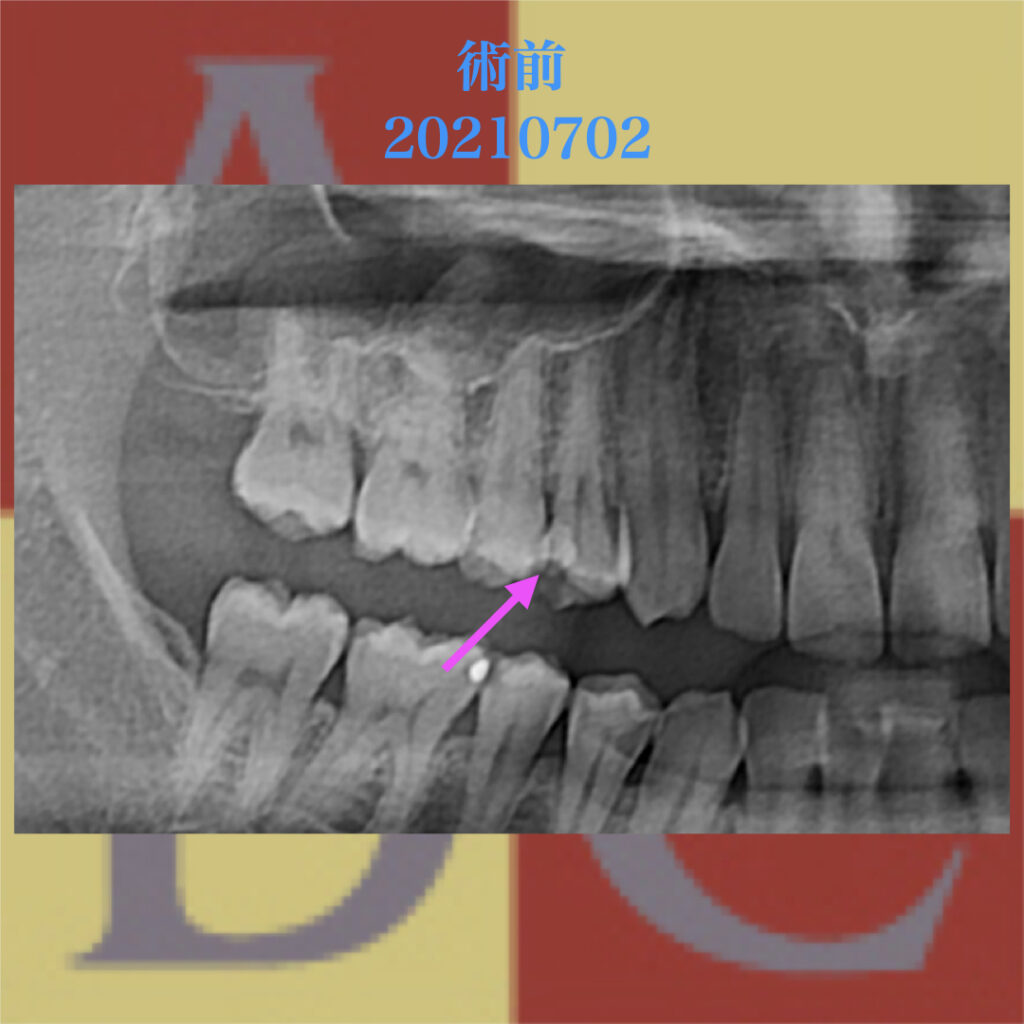

レントゲン像にて、ピンクの矢印に示された白い不透過像が浮いたCR

青い点線の部分が歯髄で、近接したCRが確認される。